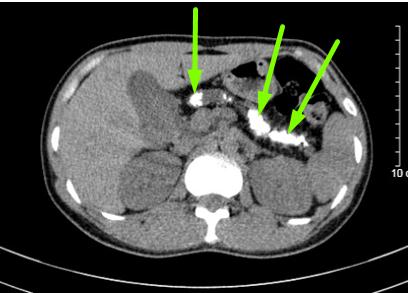

Trường hợp thứ nhất: bệnh nhân nam N.V.B 50 tuổi, có thói quen uống rượu từ năm 20 tuổi, mỗi ngày trung bình 150ml. Đợt này anh B thấy đau bụng âm ỉ quanh rốn, thượng vị, ở nhà tự mua thuốc giảm đau không đỡ. Một tháng gần đây, anh đau bụng tăng lên kèm ăn uống kém. Qua bạn bè giới thiệu, anh B đến khám tại phòng khám của Khoa Phẫu thuật tiêu hóa – Gan mật tụy. Phim chụp cắt lớp vi tính cho thấy hình ảnh nhu mô tụy teo nhỏ, ống tụy giãn 1 cm và trong có rất nhiều sỏi. Người bệnh được chẩn đoán sỏi tụy/viêm tụy mạn – nghiện rượu và được phẫu thuật theo phương pháp Frey (mở dọc ống tụy từ đầu đến đuôi tụy, lấy tổ chức đầu tụy sinh thiết, nối tụy ruột). Sau mổ, bệnh nhân được sử dụng hệ thống giảm đau, kết hợp vận động sớm sau mổ và can thiệp dinh dưỡng. Bệnh nhân B được ra viện sau 7 ngày phẫu thuật. Hiện tại, tình trạng bệnh nhân ổn định, hết đau bụng, ăn uống sinh hoạt bình thường, đã bỏ rượu theo tư vấn của bác sĩ.

Hình 1: Ảnh trên cắt lớp vi tính và trong mổ của bệnh nhân B

(mũi tên chỉ sỏi tụy)